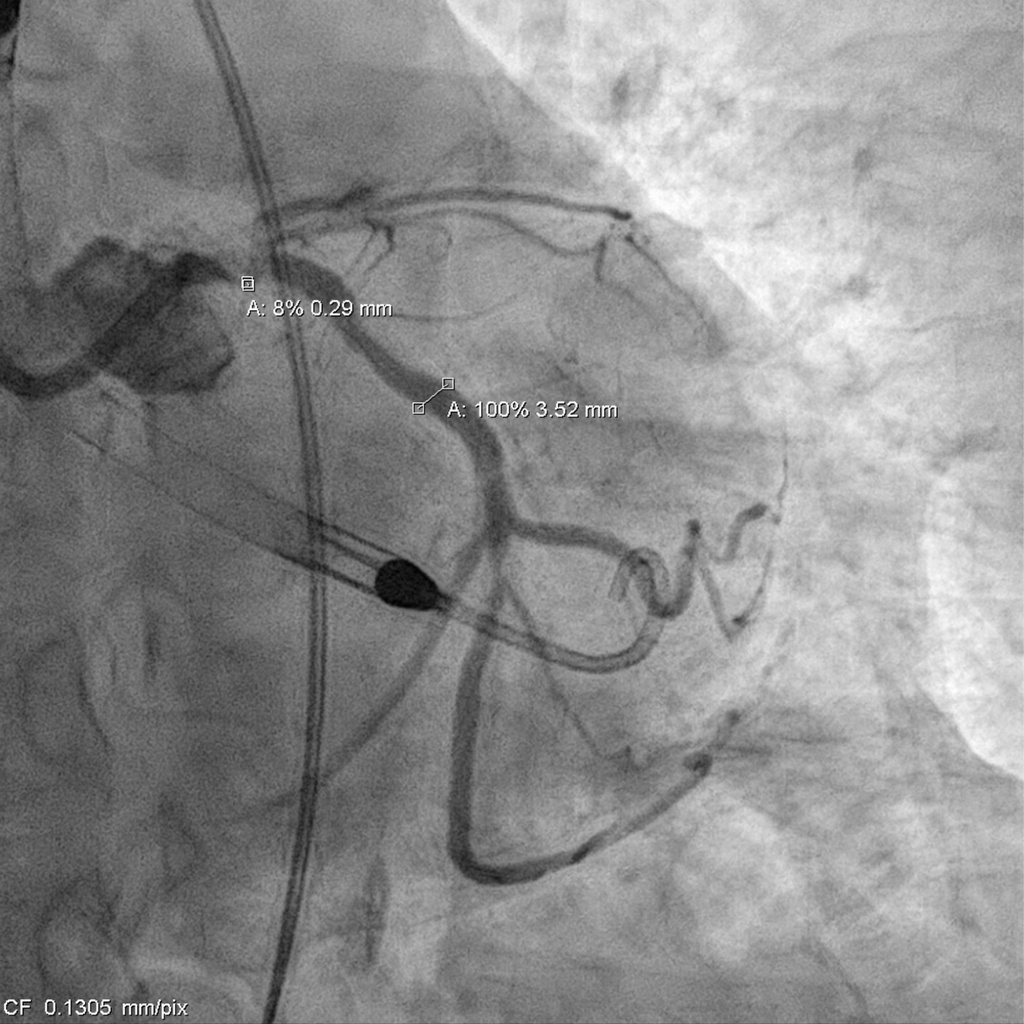

Catheterization revealed a 95% distal left main stenosis with a calcified nodule protruding into the LAD and LCX ostia, a 99% proximal LAD lesion with an additional 90% stenosis after the first diagonal branch, non-critical LCX disease, and a 70% proximal RCA lesion with multiple critical PDA stenoses. The patient and family declined PCI in the cath lab, with a Syntax score of 40.

Impella support was established before the procedure. The LCA was engaged with an EBU 3.0 ¡¿ 7 Fr guide, and a SUOH-03 wire was advanced into the LCX. A 2.0 ¡¿ 20 mm balloon was inflated across the very tight LM–LCX lesion, but IVUS still could not cross, so rotablation was performed first. The SUOH-03 wire was exchanged for a Rota Floppy using a Caravel microcatheter, and a 2.0 mm burr successfully ablated the heavily calcified, angulated LM–LCX segment.After calcium modification, a Fielder FC wire was advanced into the LAD using a reverse-wire technique. Severe mid-LAD calcification required switching to a Rota Floppy wire, and a 1.25 mm burr was used for LAD rotablation. Bradycardia occurred during Rota, so a temporary pacemaker was inserted. A 2.25 ¡¿ 15 mm NC balloon was then inflated to 12 atm to further prepare the LAD.The LAD was stented with an Onyx 2.25 ¡¿ 22 mm DES (6–16 atm) and subsequently crushed with a 3.5 ¡¿ 12 mm NC balloon. LM–LCX was stented with an Onyx 3.5 ¡¿ 15 mm DES (11–12 atm). LAD was rewired with a Sion Blue supported by a Crusade dual-lumen catheter, and stent struts were opened using 1.5 ¡¿ 10 mm and 2.5 ¡¿ 15 mm balloons. LAD-P was post-dilated with a 2.5 ¡¿ 15 mm NC (10 atm), and LM–LAD with a 2.5 ¡¿ 15 mm NC (12–18 atm). Final kissing inflation with a 3.5 ¡¿ 12 mm NC and 2.5 ¡¿ 15 mm NC balloons achieved optimal flow.The Impella was removed under stable hemodynamics, and the access site was closed with two Perclose devices without bleeding.